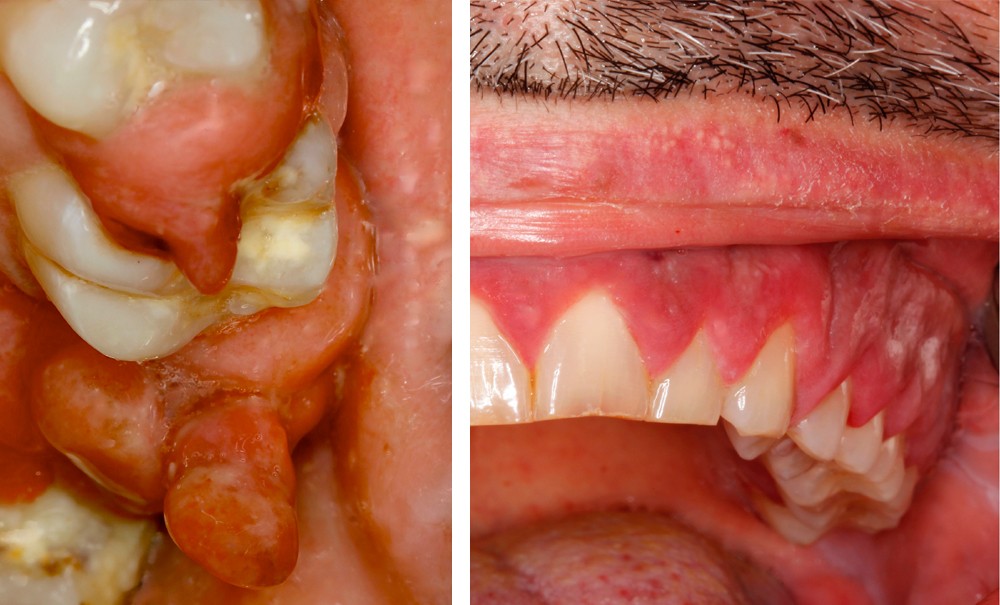

• On observait une hyperplasie gingivale intéressant les 4 régions molaire-prémolaire, avec des dents plus ou moins mobiles ; les secteurs antérieurs étaient épargnés. Cette hyperplasie gingivale était par endroits très volumineuse et prenait parfois l’aspect d’un granulome pyogénique.

• L’hyperplasie gingivale était revêtue par un épithélium malpighien kératinisé, irrégulier, comportant quelques ulcérations superficielles. Les crêtes épithéliales étaient par endroits discrètement hyperplasiques…